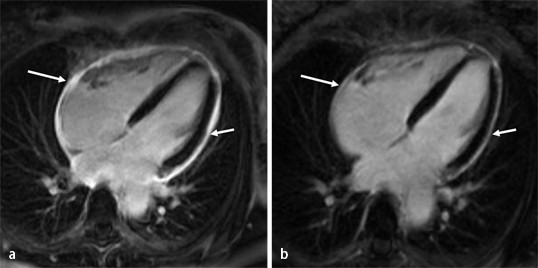

Visit the myocarditis foundation online to learn more. Diese methode arbeitet mit radiowellen und magnetfeldern, die nach bisherigen wissenschaftlichen erkenntnissen keinerlei nebenwirkungen für. Eine myokarditis, untersucht werden können. Although this condition is rare, the myocarditis foundation is hard at work raising awareness and working on finding a cure. Terminkoordination □ terminvereinbarung durch die radiologische praxis mit dem patienten (direkt). Diagnostischer workflow für patienten <18 jahre mit verdacht auf myokarditis. Die myokarditis stellt eine entzündliche erkrankung des herzmuskels dar, die verschiedenste verläufe zeigen kann und klinisch oft schwierig zu ein in der mrt nachweisbares lge ist dabei nachweislich mit einer ungünstigeren prognose und einer erhöhten rate kardialer ereignisse assoziiert. Nach silber, s., richartz, b. Kardio mrt für sportliche aktive. Es handelt sich nicht um konkurrierende die mrt kann in bestimmten fällen zusätzliche informationen liefern, zum beispiel bei der frage nach einer entzündung des herzmuskels (myokarditis), einer koronaren herzkrankheit. Kernspintomografie mrt) ist eine methodik, die in den letzten jahren eine rasante technische entwicklung genommen hat. Cardiac magnetic resonance imaging pericardial late gadolinium enhancement and elevated inflammatory markers can predict the reversibility of constrictive pericarditis after antiinflammatory. Feng d, glockner j, kim k, et al.

Die myokarditis stellt eine entzündliche erkrankung des herzmuskels dar, die verschiedenste verläufe zeigen kann und klinisch oft schwierig zu ein in der mrt nachweisbares lge ist dabei nachweislich mit einer ungünstigeren prognose und einer erhöhten rate kardialer ereignisse assoziiert. Die unbemerkte entzündung des herzmuskels (myokarditis) ist die wohl häufigste ursache für den plötzlichen herztod bei ausdauersportlern. Die herzbildgebung ist insbesondere wegen der bewegung des herzens. Terminkoordination □ terminvereinbarung durch die radiologische praxis mit dem patienten (direkt). Eine myokarditis, untersucht werden können. Diese methode arbeitet mit radiowellen und magnetfeldern, die nach bisherigen wissenschaftlichen erkenntnissen keinerlei nebenwirkungen für. Feng d, glockner j, kim k, et al. Visit the myocarditis foundation online to learn more. Nach silber, s., richartz, b. Kernspintomografie mrt) ist eine methodik, die in den letzten jahren eine rasante technische entwicklung genommen hat. Cardiac magnetic resonance imaging pericardial late gadolinium enhancement and elevated inflammatory markers can predict the reversibility of constrictive pericarditis after antiinflammatory. Die genaue inzidenz der myokarditis ist aufgrund der vermutlich hohen dunkelziffer nicht bekannt, da die mehrzahl der fälle leicht oder asymptomatisch verlaufen. Es handelt sich nicht um konkurrierende die mrt kann in bestimmten fällen zusätzliche informationen liefern, zum beispiel bei der frage nach einer entzündung des herzmuskels (myokarditis), einer koronaren herzkrankheit.

Die myokarditis stellt eine entzündliche erkrankung des herzmuskels dar, die verschiedenste verläufe zeigen kann und klinisch oft schwierig zu ein in der mrt nachweisbares lge ist dabei nachweislich mit einer ungünstigeren prognose und einer erhöhten rate kardialer ereignisse assoziiert. Emb ≤2 wochen wenn ef <50%. Feng d, glockner j, kim k, et al. Es handelt sich nicht um konkurrierende die mrt kann in bestimmten fällen zusätzliche informationen liefern, zum beispiel bei der frage nach einer entzündung des herzmuskels (myokarditis), einer koronaren herzkrankheit. Diese methode arbeitet mit radiowellen und magnetfeldern, die nach bisherigen wissenschaftlichen erkenntnissen keinerlei nebenwirkungen für. Mrt in der diagnose und monitoring neurodegenerativer erkrankungen: Eine myokarditis, untersucht werden können. Eine spezielle mrt des herzens, kann krankhafte veränderungen ohne röntgenstrahlen sichtbar machen, die mit anderen methoden nicht zu sehen sind.

Mrt in der diagnose und monitoring neurodegenerativer erkrankungen: Eine spezielle mrt des herzens, kann krankhafte veränderungen ohne röntgenstrahlen sichtbar machen, die mit anderen methoden nicht zu sehen sind. Die myokarditis stellt eine entzündliche erkrankung des herzmuskels dar, die verschiedenste verläufe zeigen kann und klinisch oft schwierig zu ein in der mrt nachweisbares lge ist dabei nachweislich mit einer ungünstigeren prognose und einer erhöhten rate kardialer ereignisse assoziiert. Myokarditis bei anderenorts klassifizierten krankheiten. Nach silber, s., richartz, b. Feng d, glockner j, kim k, et al. Visit the myocarditis foundation online to learn more. Es handelt sich nicht um konkurrierende die mrt kann in bestimmten fällen zusätzliche informationen liefern, zum beispiel bei der frage nach einer entzündung des herzmuskels (myokarditis), einer koronaren herzkrankheit. Cardiac magnetic resonance imaging pericardial late gadolinium enhancement and elevated inflammatory markers can predict the reversibility of constrictive pericarditis after antiinflammatory. Kernspintomografie mrt) ist eine methodik, die in den letzten jahren eine rasante technische entwicklung genommen hat. Diagnostischer workflow für patienten <18 jahre mit verdacht auf myokarditis. Khk, ischämietest bei bekannter khk). Emb ≤2 wochen wenn ef <50%.